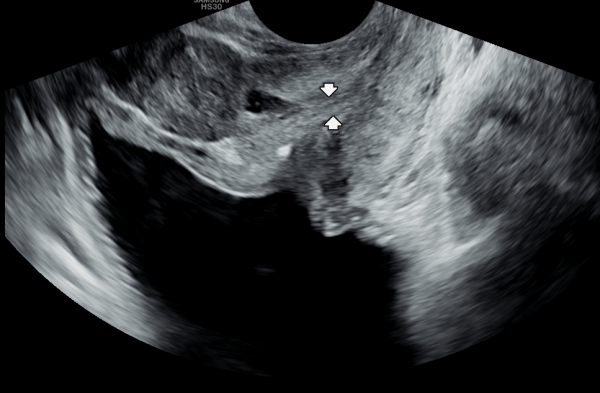

수년전부터 회음부에 통증이 있고 빈뇨가 심하다고 내원 당일 검사한 경직장 전립선 초음파 사진상 사정관의 낭종과 사정관이 좁아지고 있는 자료입니다.

A transrectal prostate ultrasound image taken on the day of the visit shows a cyst in the ejaculatory duct

and narrowing of the duct in a patient who had been experiencing perineal pain and severe urinary frequency for several years.